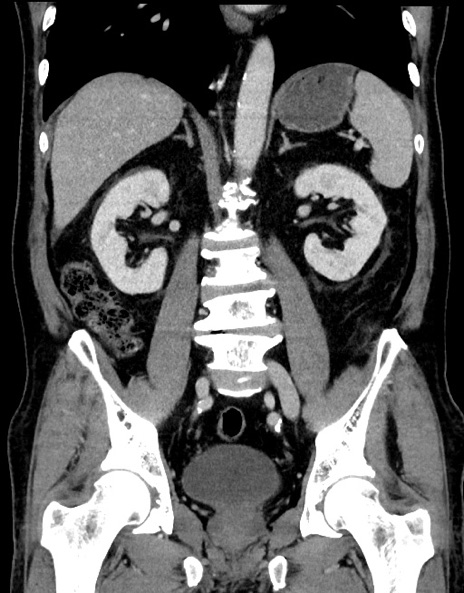

症例15(冠状断像)

【症例】70歳代男性

【主訴】腹痛

【現病歴】今朝から腹痛あり。全体的に痛い。特に左上の方。排ガスが今日はない。冷や汗が出る。

【既往歴】直腸癌術後

【身体所見】左側腹部〜上腹部に圧痛あり。腹膜刺激症状明らかなではない。軽度反跳痛。左下腹部に術後瘢痕あり。

【データ】WBC 7700、CRP 0.02